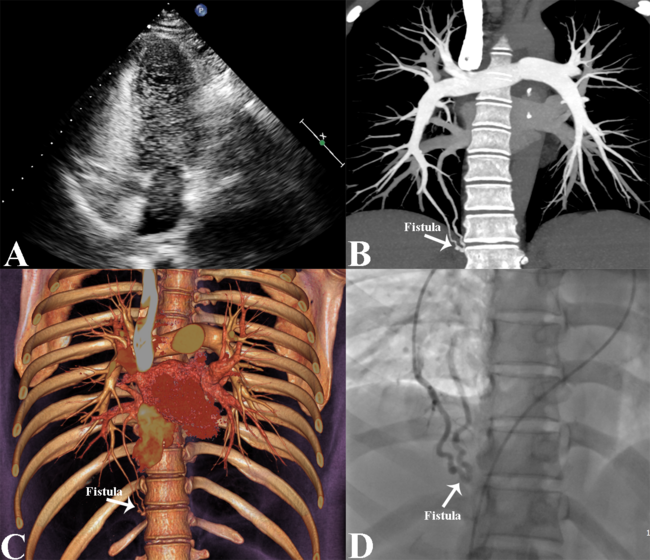

A 39-year-old woman presented with a recurrent headache and dizziness for 6 months. Physical examination and laboratory tests were unremarkable, and an electrocardiogram indicated sinus rhythm. Transthoracic echocardiography (TTE) showed normal heart morphology, structure, function, and hemodynamics. TTE with a microbubble test showed a grade 3 right-to-left shunt after 6 cardiac cycles (Figure A, Video 1). A pulmonary arteriovenous fistula (PAVF) was suspected. Computed tomography pulmonary angiography (CTPA) showed a small right inferior PAVF (Figure B, C). Pulmonary angiography detected a 4-mm PAVF flowing into the right inferior pulmonary vein (Figure D, Video 2). This PAVF was successfully embolized by a SQFDQ-II Muscular VSD Occluder and its delivery system (Shanghai Shape Memory Alloy Co., Ltd.); the thickness of the occluder waist was 8 mm. After this procedure, selective pulmonary arteriography showed no residual shunt (Video 3). The postoperative course was uneventful, and the patient was discharged after 3 days. At the 6-month follow-up, the patient's symptoms had disappeared completely.